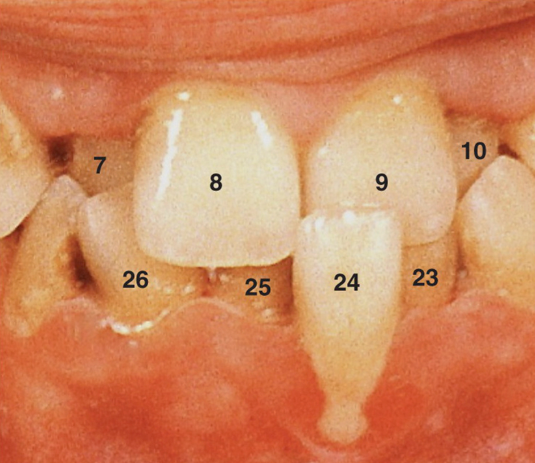

<p>50. What terminology would you use to describe the location of tooth #24 seen in Fig. 5.31?</p><p>a. Torsiversion</p><p>b. Infraocclusion</p><p>c. Labioversion</p><p>d. Linguoversion</p>

50. What terminology would you use to describe the location of tooth #24 seen in Fig. 5.31?

c. Labioversion

<p>8. Looking at Fig. 5.25, what gingiva is edematous?</p><p>a. Gingival margin</p><p>b. Attached gingiva</p><p>c. Interdental papilla</p><p>d. a. and c.</p>

8. Looking at Fig. 5.25, what gingiva is edematous?

d. a. and c.